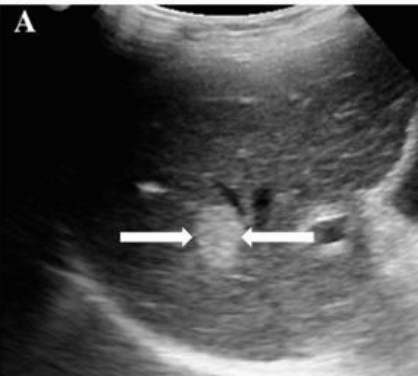

2~3cm hcc sono features ③ 3~5 cm hcc sono finding

- hypo-hyperechoic

- heterogenous

- irregular

- hump sign (표면에 존재하는 결절형 종괴에서 간표면으로 종괴가 돌출하는 경우 나타난다)

- mosaic pattern (종양내부에 괴사나 출혈이 생겨 내부에 균열이 있는 것처럼 보이는 모자이크패턴이 나타남)

- color doppler : internal mass pattern (feeding artery)

감별진단

- FNH

- Adenoma